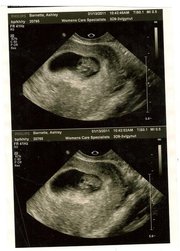

Grandpa....I am about to become one.

Seriously! What does that mean?

It means that my heart capacity has grown exponentially since I first heard the news.

It means that I will hold in my arms what I have always desired in my heart.

It means that I will add one more name to the list of things that I talk to God about.

It means that what little money I have will have one more place to go.

It means that I will lay awake at night thinking about all of the stories I will tell.

Oh, by the way...I am planning on taking off August 27th this year...maybe even a few days before and after.